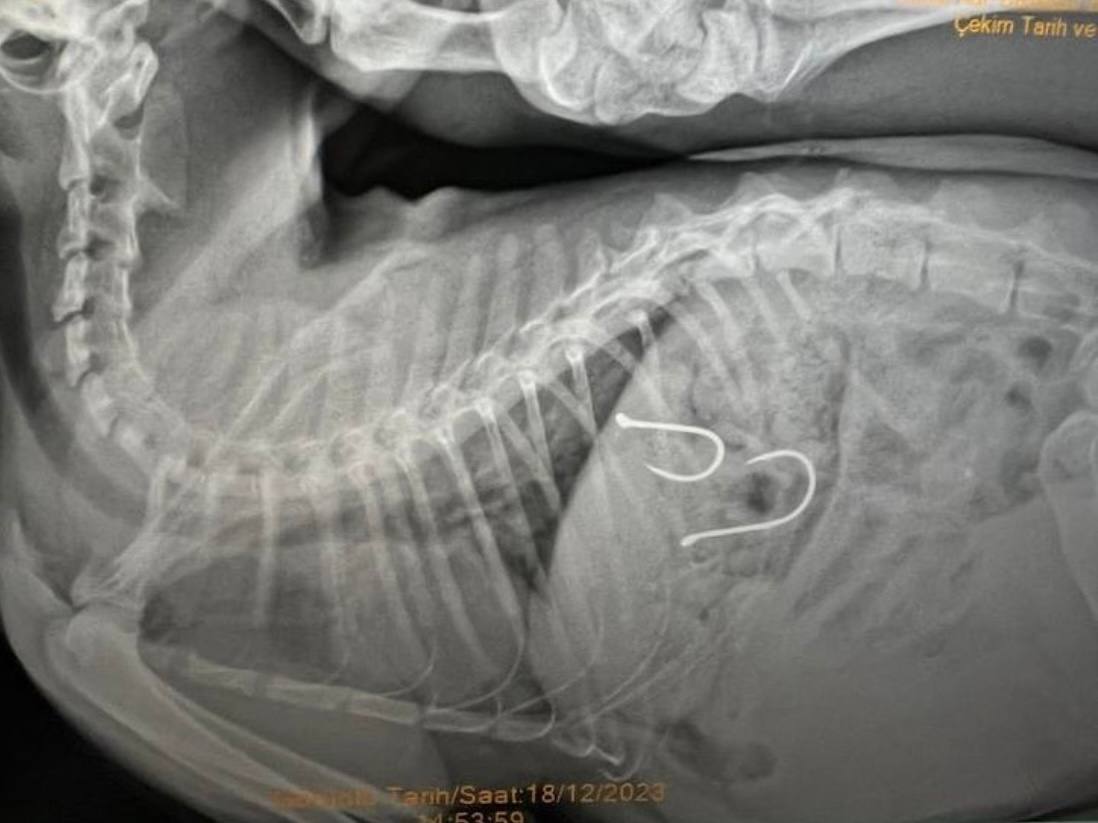

Sahil bandında dolaşan vatandaşlar bir kedinin ağzından olta misinası sarktığını fark edince durumu Balıkesir Büyükşehir Belediyesi Sokak Hayvanları Tedavi Merkezi’ne ihbar etmişlerdi. Gelen ihbar üzerine, kedi ekipler tarafından müşahede altına alınmış ve sağlık durumu kritik olan yaralı hayvana acil olarak müdahale eden edilmişti. Çekilen röntgen sonucunda olta iğnelerinin kedinin midesine saplandığı anlaşılmış ve sonrasında ise kedi ameliyata alınmıştı.

Kedinin sağlık durumu ile ilgili Balıkesir Büyükşehir Belediyesi Sokak Hayvanları Tedavi Merkezi’nden edinilen son bilgilere göre, 2 adet olta iğnesi ve misinasının kedinin midesinden başarılı bir operasyonla çıkarıldığı, olta kancasının enfeksiyon oluşturma riskine karşı, antibiyotik ve serum tedavisine başlandığı belirtildi. Kedinin genel sağlık durumunda şu an için bir olumsuzluğun söz konusu olmadığı ve 48 saat yoğun bakımda tutulacağı söylendi.